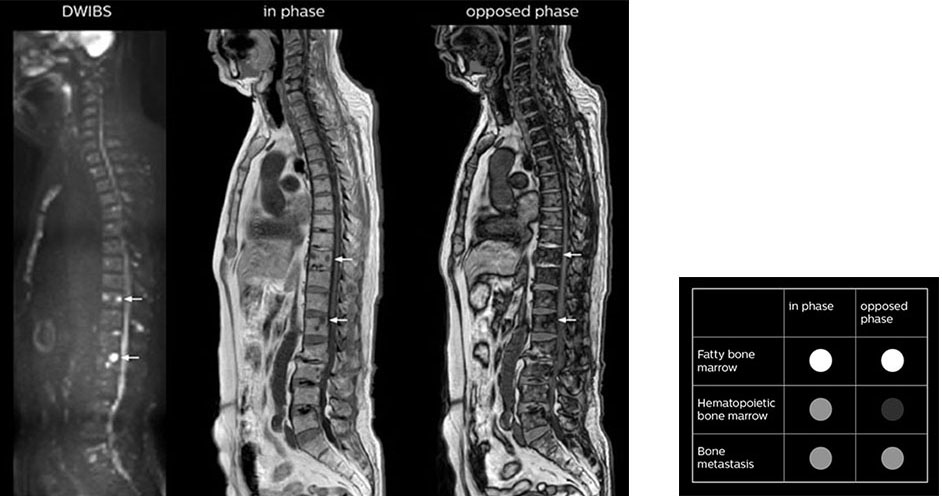

“In-phase and out-phase sagittal T1-weighted FFE images help us to visualize and further characterize bone lesions such as metastasis and bone-marrow hyperplasia that have high signal on DWI. These images are also used throughout radiotherapy, to monitor changes in the fatty bone marrow.”